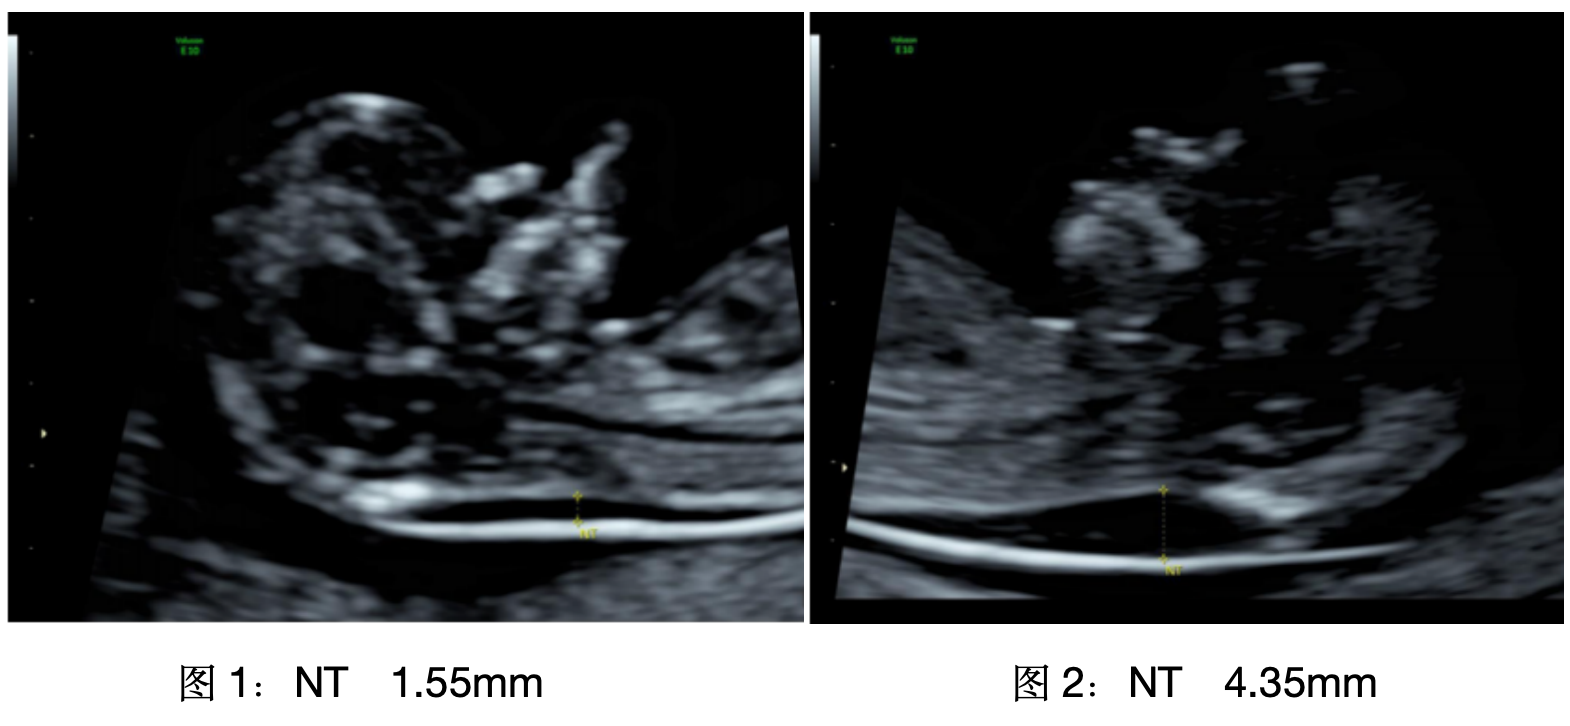

01測測寶寶的NT

這是早期評估胎兒染色體異常風(fēng)險的重要指標(biāo),NT增厚也是嚴(yán)重心臟畸形、遺傳綜合征等異常的早期表現(xiàn)。